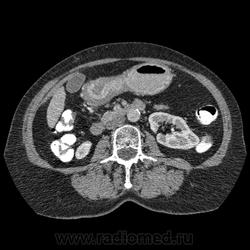

Впечатление, что дуля эта вне головки п.ж., интрамурально в луковице, что ли... тогда возможно GIST, но надо дайком. Утолщение подслизистой в антральном отделе желудка, не удается проследить переход от желудка к 12-перстной((. Внутрипросветно/внутристеночно - не разобрать. 1 фаза?

Клинику! Есть ли признаки высокой тонкокишечной непроходимости, что при ФЭГДС в 12-перстной - туда удалось пройти или нет? ААА! Одни вопросы))))

В-общем, варианты такие без дайкомов: пролапс слизистой в 12перстную, безоар, внутрипросветный дивертикул, гастроинтерстинальная опухоль. И большие сомнения, что это в головке п.ж. - оно отделено от неё тонким слоем жировой клетчатки

Фаз было 3. Видео не выставлял прошлый раз пришел ответ из сайта что видео не работает на сайте Идет накопление контраста в нативе в центре +2+4 по периферии +32+34 .в артериальную +20 и +65 +70 соответственно.

Что оно копит - бог с ним... если это пролапс слизистой, то суммация стенок. Безоар бы не копил. Напрягает отек слизистой в антрале... Это должно быть скорее внутри просвета кишки, т.к. оттесняет газ в 12-перстной на периферию. Без дайкомов больше ничем не могу, извините. Подождём мнения коллег.

Как мне видится - пролапс слизистой желудка в 12-перстную. А мнения коллег что-то нетути...

А что растет из левой почки? Может оно же и желудок сдавливает?

Это расширение всей 12- перстной кишки (стаз).